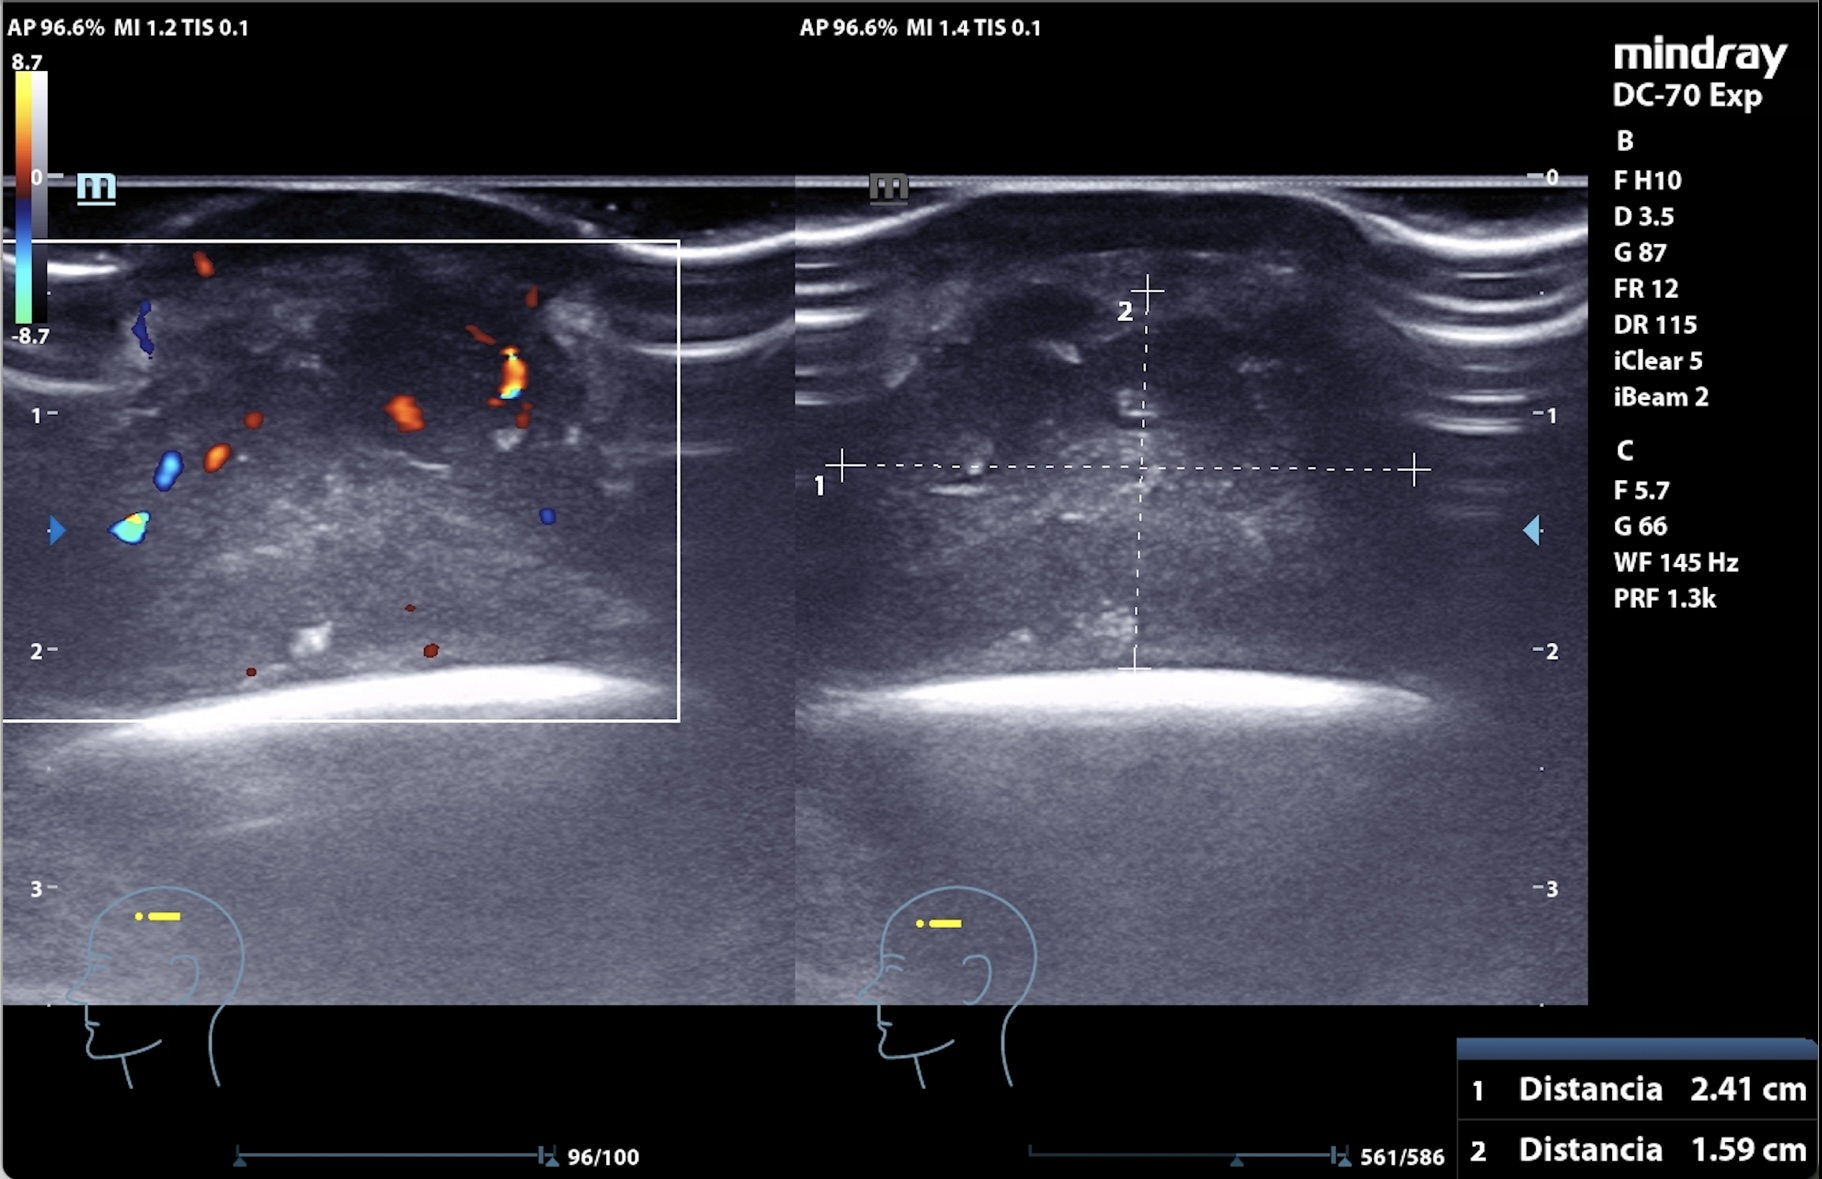

Se realiza en consulta ecografía, donde, para evitar la contaminación, se utiliza una funda estéril con gel conductor en su interior y clorhexidina entre la sonda y el cuero cabelludo como conductor líquido.

La imagen muestra una lesión heterogénea, con bordes netos, pero sin cápsula, microcalcificaciones en su interior y zonas hipoanecogénicas de necrosis líquida interna, así como vascularización interna intensa en Doppler. El patrón sugería proceso infiltrativo, por lo que se priorizó derivación urgente a dermatología.